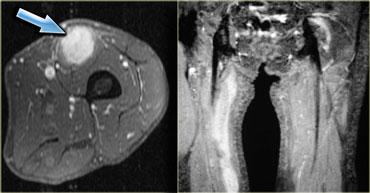

Hình bên trái là một bệnh nhân khác với viêm cơ nốt khu trú, trông giống như bất kỳ khối nào khác trên chuỗi xung T1W, T2W và sau tiêm thuốc tương phản từ.

Với tiền sử u lympho, có thể gợi ý viêm cơ nốt khu trú, nhưng không có gì mang tính quyết định từ các hình ảnh này.

2 loại ung thư có mối liên hệ với viêm cơ: ung thư buồng trứng và u lympho không Hodgkin

(hình bên trái là bệnh nhân với, thật kỳ lạ, ung thư tuyến giáp di căn).

Viêm cơ có thể xuất hiện trước bệnh ác tính (như trong hội chứng cận u), điều này không có nghĩa là cần tầm soát ác tính thường quy

ở bệnh nhân biểu hiện viêm cơ.